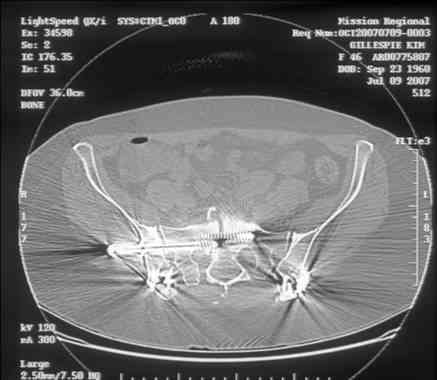

Here is a magnified view. Sorry about the quality but the CT was scanned into our system.

dave